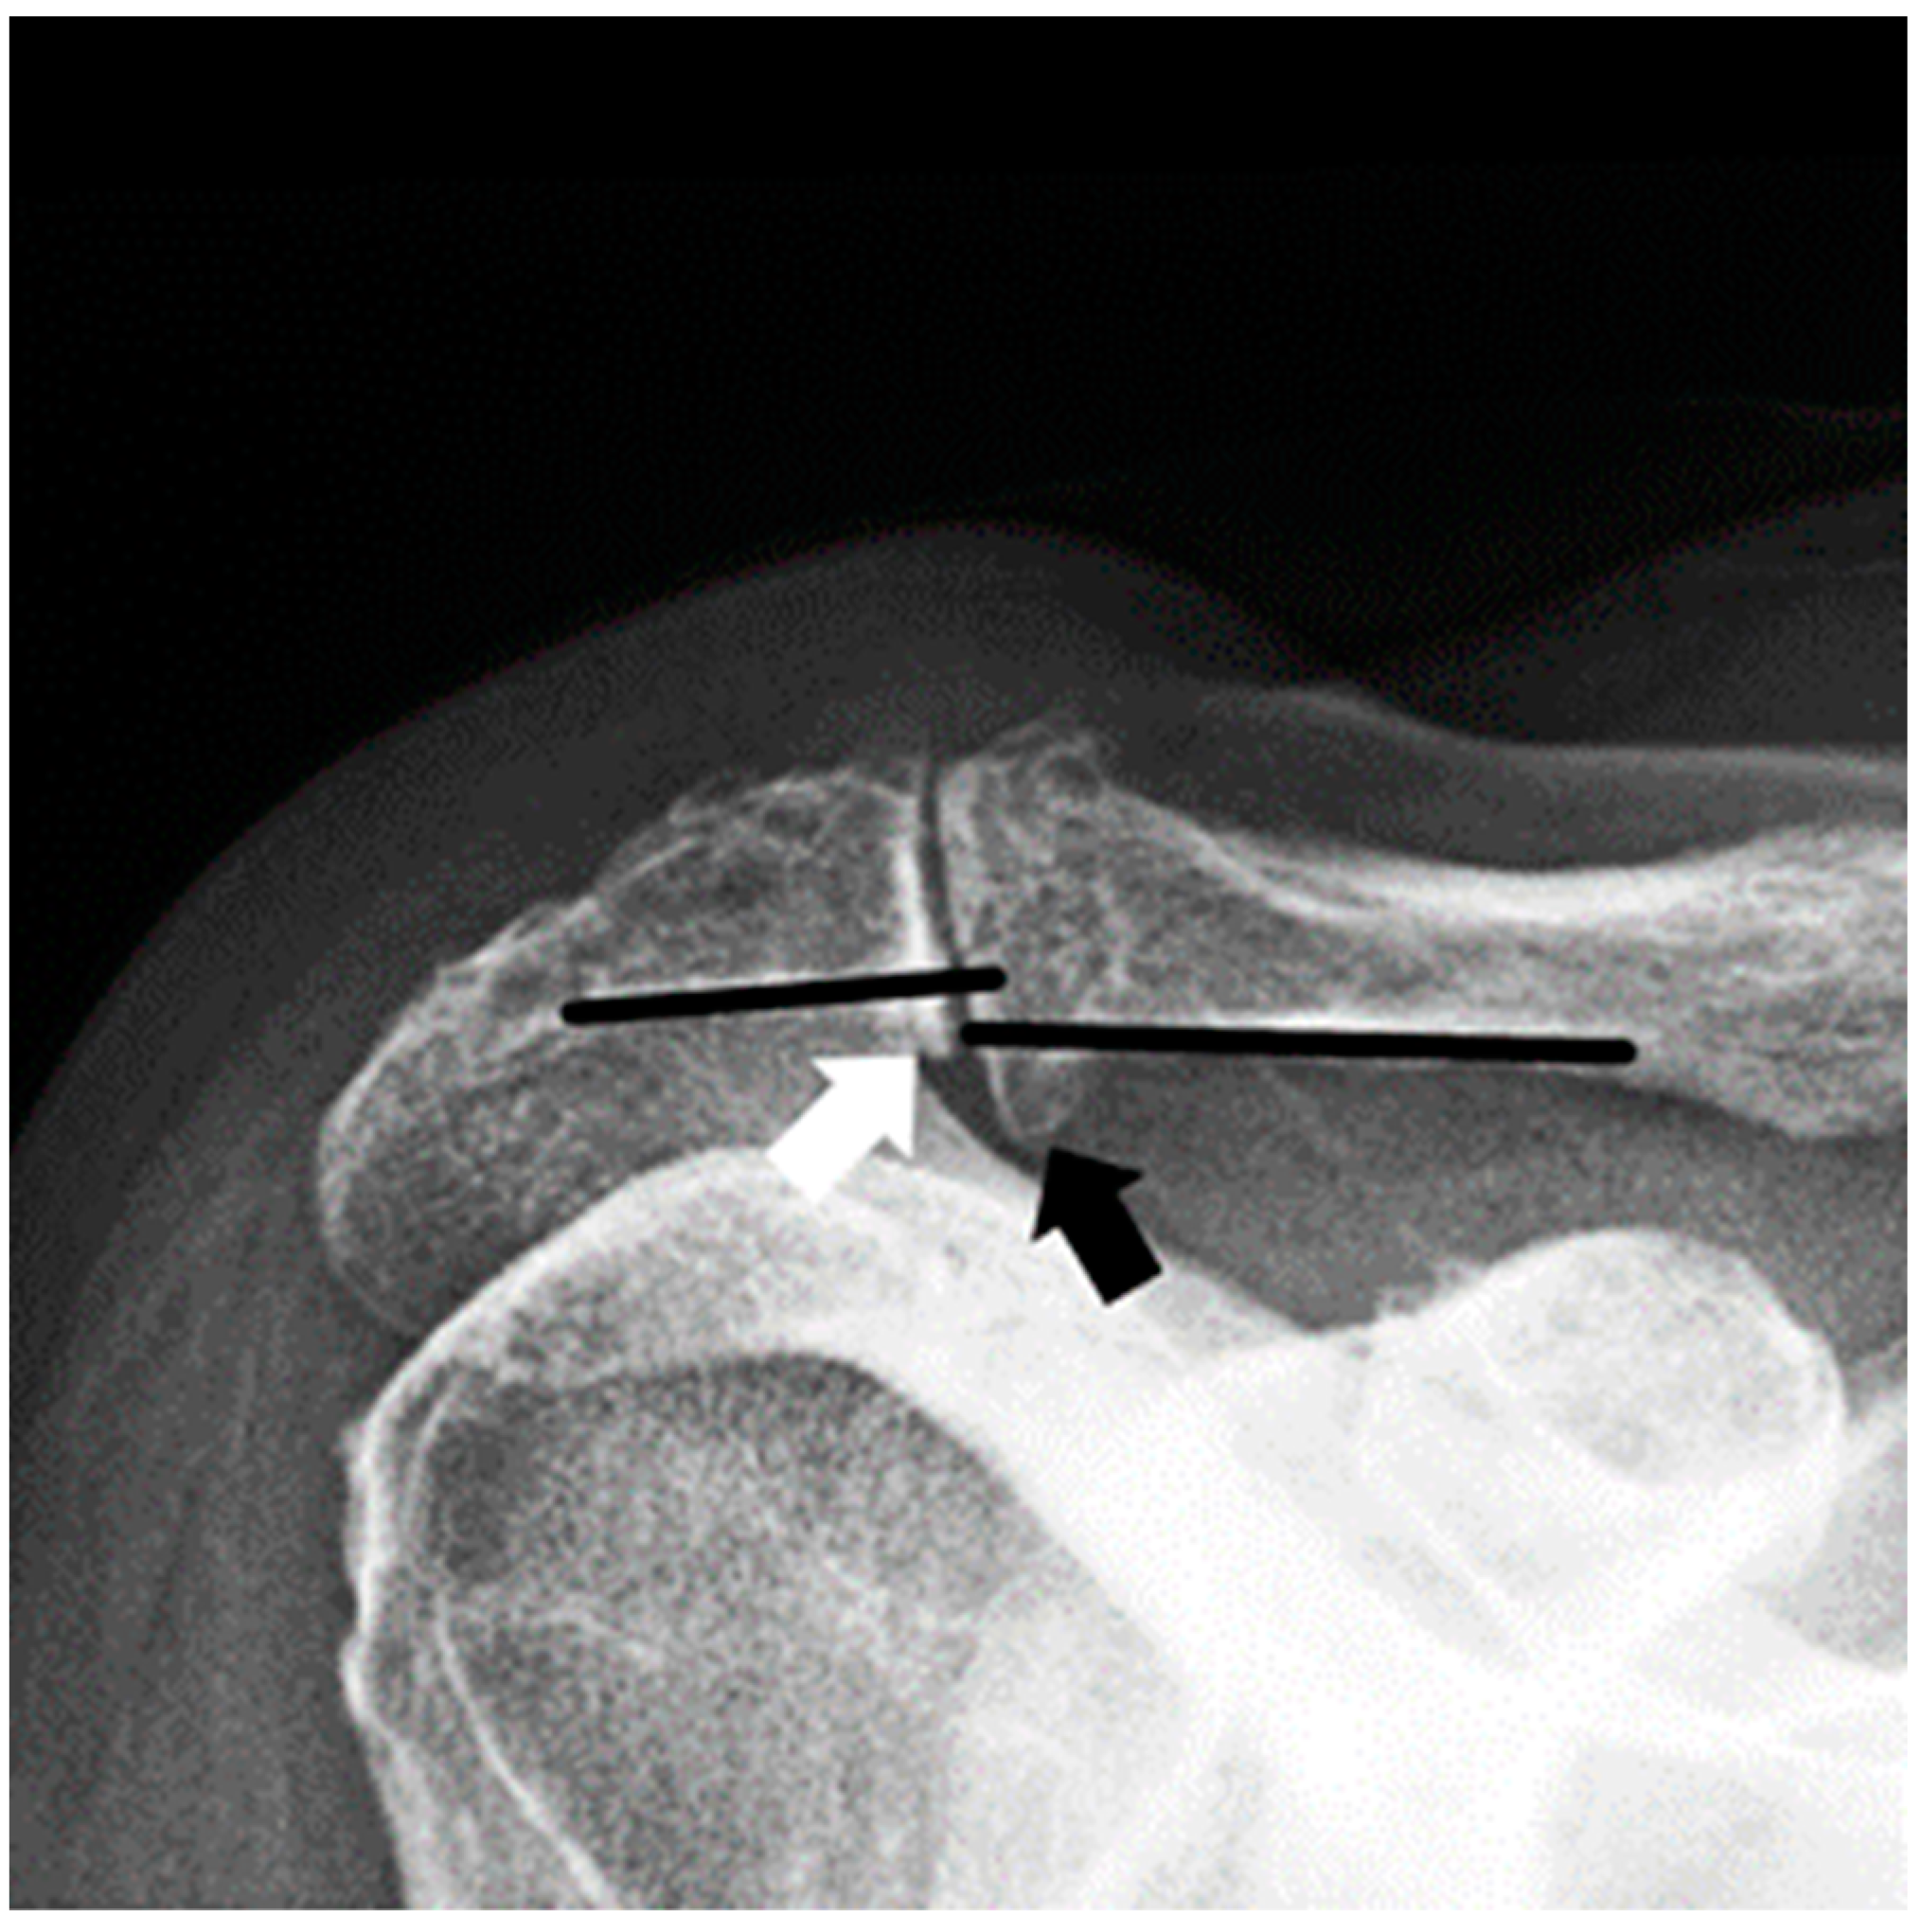

3.1. Radiographic Assessment